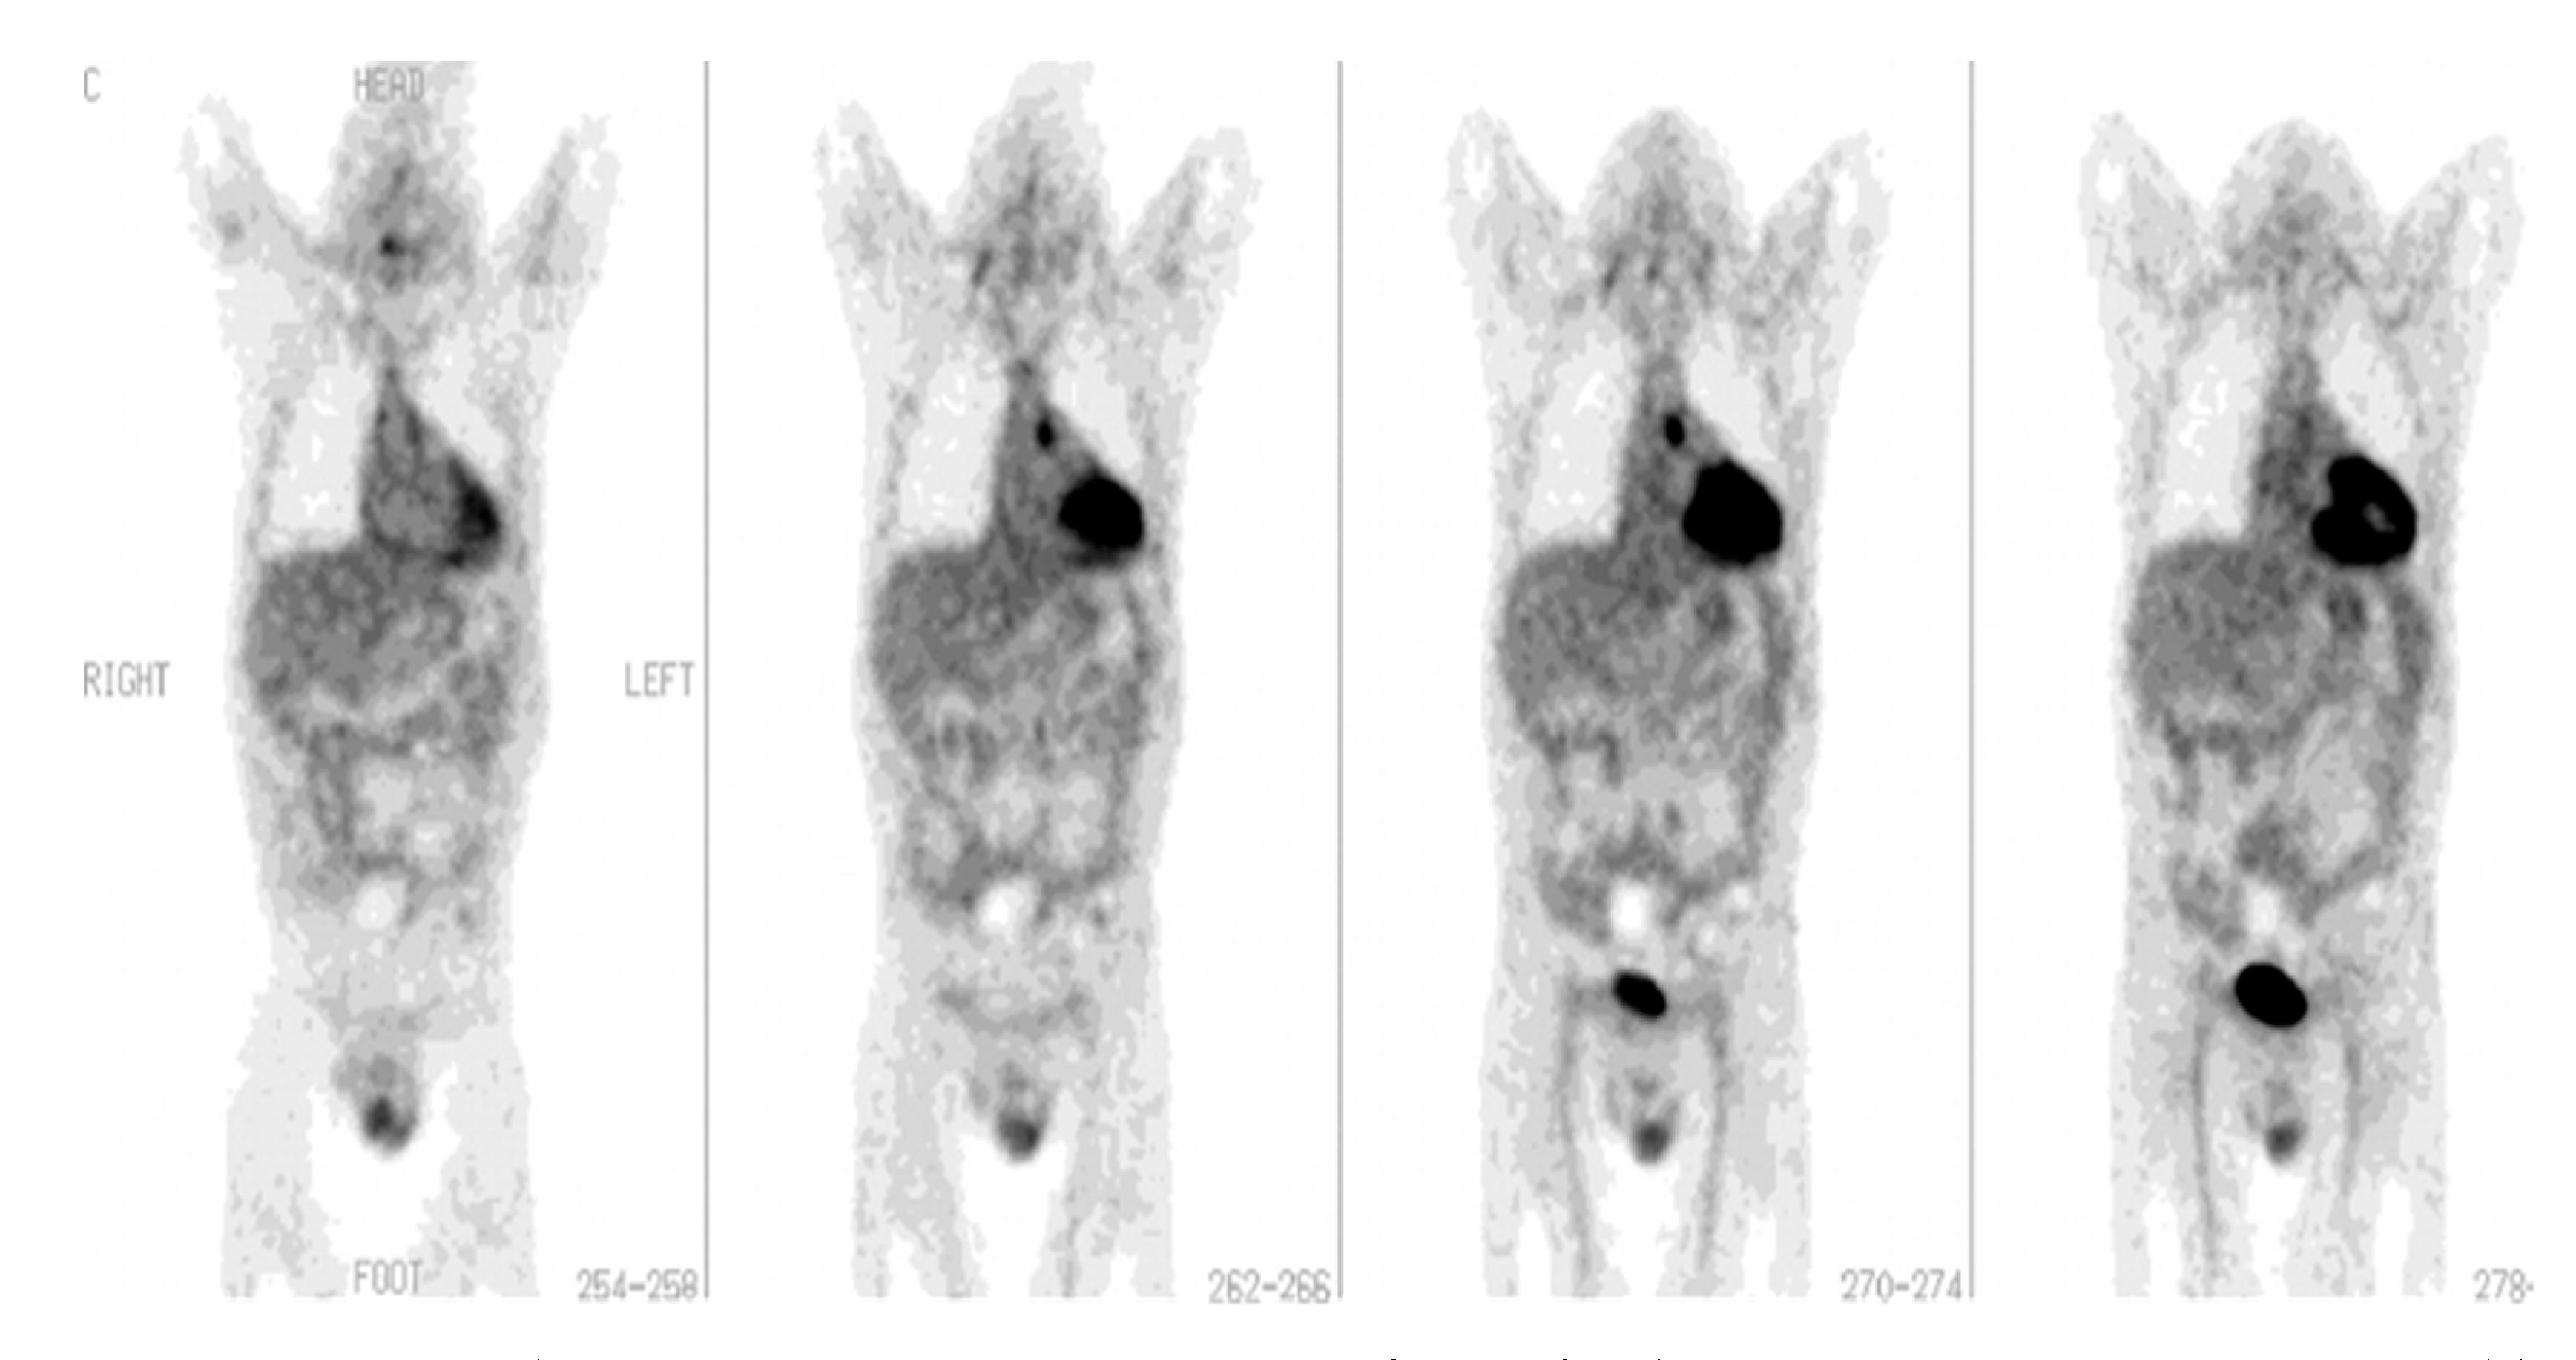

The role of [18F]FDG-PET/CT has been found to be promising in a number of musculoskeletal infectious disorders. [18F]FDG-PET/CT is important for diagnosing persistent musculoskeletal infections [45] including the detection of chronic osteomyelitis [46] (Figure 4). Some other uses of [18F]FDG-PET/CT may include evaluation of the diabetic foot [47], implant-related infections in the leg [48], and septic arthritis [44,49,50,51,52].

Figure 4. [18F]FDG-PET in osteomyelitis. Osteomyelitis of the right femur. An [18F]FDG-PET scan was recommended for a 12-year-old patient with bacteremia and right knee pain instead of labeled leukocyte imaging due to leukopenia. On the coronal (left) and axial (right) images, there is focal hypermetabolism (SUV max: 2.5) in the lateral condyle of the right femur (arrow) (with permission from [44]).